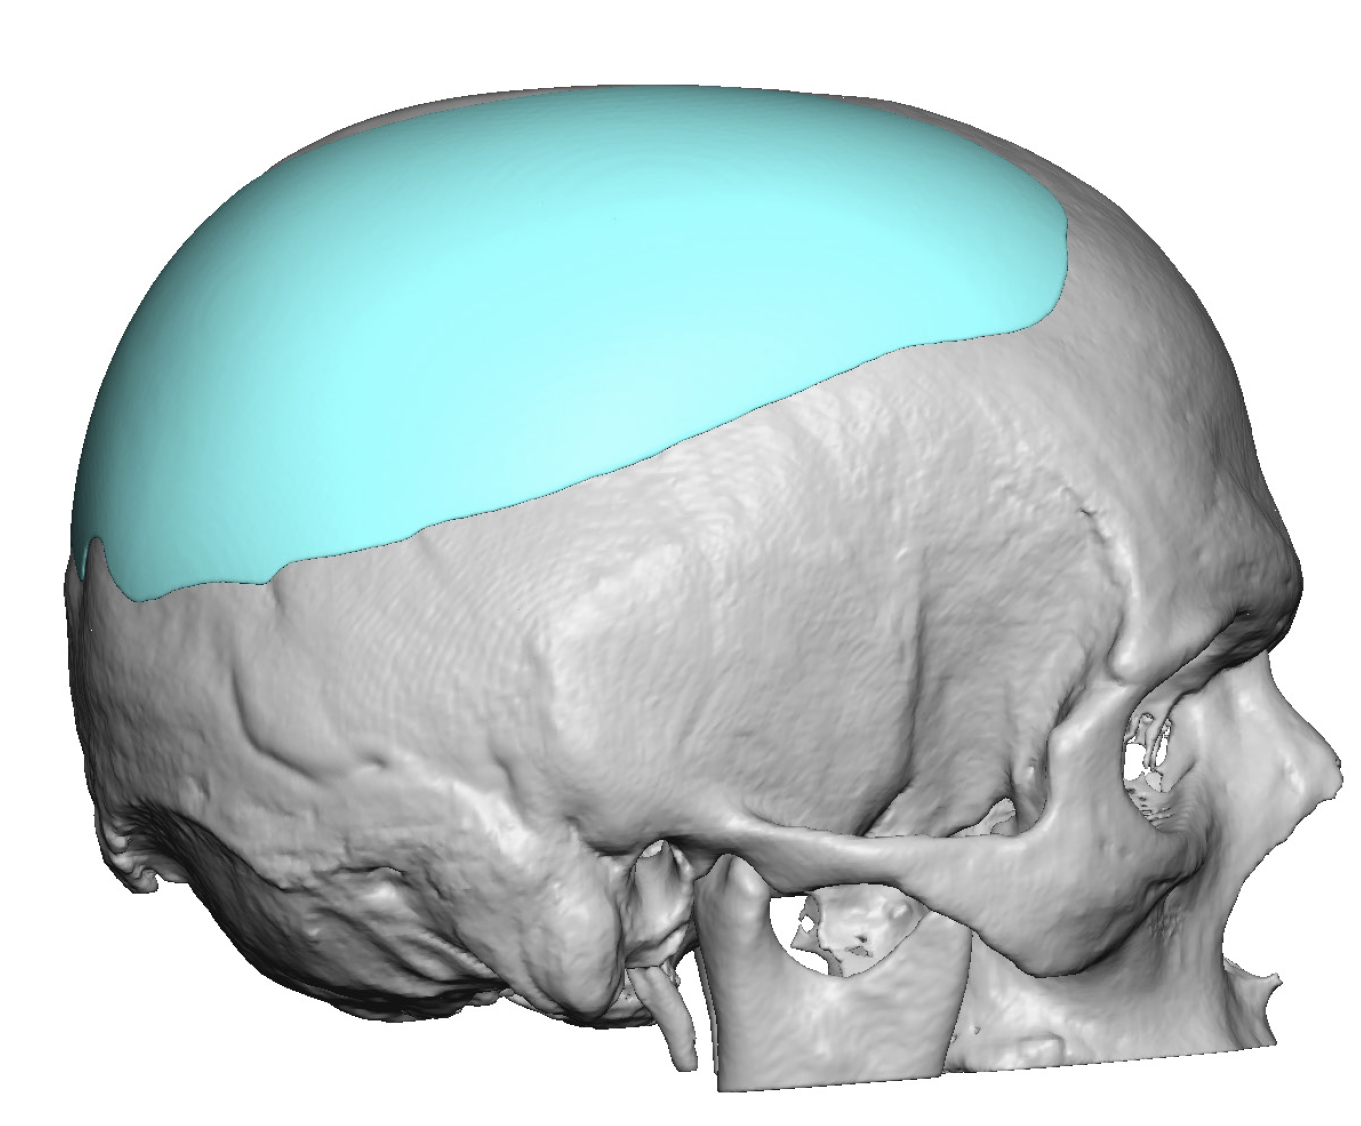

Patient 28

Desire for rounder shape to the top of the head from a congenital parasagittal deficiency skull shape.

Custom skull implant designed to fill in the parasagittal deficiencies.

Desire for rounder shape to the top of the head from a congenital parasagittal deficiency skull shape.

Custom skull implant designed to fill in the parasagittal deficiencies.